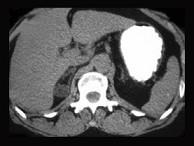

问题 肾上腺皮质腺瘤患者,已行腺瘤切除术,术后使用可的松替代治疗的时间多为()

选项 A.1个月 B.1~6个月 C.6~12个月 D.1~2年 E.长期

答案 C